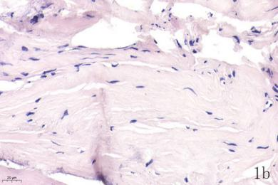

NDN(Necdin)属于黑色素瘤抗原(MAGE)家族,由60多个基因构成共享高度保守的MAGE同源结构域(MHD)[6,7]。最近几年的研究提出NDN是一种新的抑癌基因,其在卵巢癌[8]、乳腺癌[9]和黑色素瘤[10]等的组织和细胞系中低表达,过表达NDN可以抑制其生长,但NDN在骨肉瘤中的作用及机制尚不清楚。为探讨NDN在骨肉瘤中的作用及途径,我们收集了骨肉瘤患者的石蜡标本以及临床信息,对其进行了免疫组化检测及生存分析通过对骨组织和骨肉瘤HE染色发现,骨组织组,骨密质呈板层状,陷窝中可见骨细胞呈梭形排列( 图1 a 1b) ;骨肉瘤组,瘤细胞呈多角形,核大深染,核分裂多见,瘤细胞呈车辐状排列,瘤细胞间可见少量肿瘤性骨质形成(图1c1d)。同时通过免疫组化发现,NDN表达主要位于细胞的胞核中。NDN在骨肉瘤组织中的表达率为29.4%(15/51)(图1c1d),明显低于瘤旁骨组织阳性表达率80%(8/10)(图1a1b)。